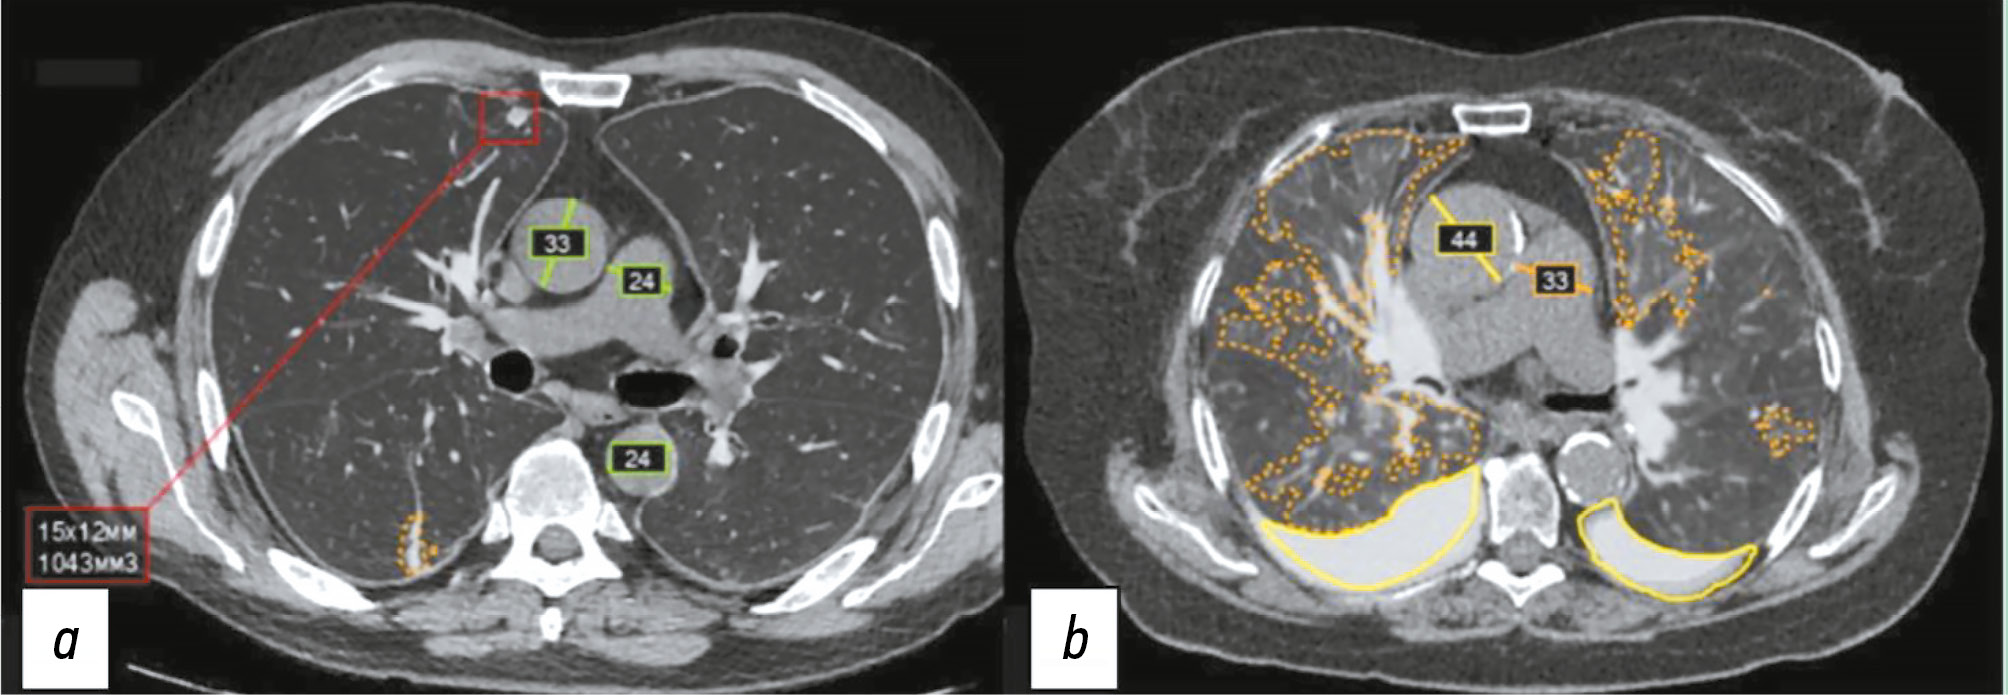

Тем не менее систематический (организованный) скрининг аневризм и дилатаций грудной аорты отсутствует [111]. Пример работы системы ИИ в рамках Московского эксперимента продемонстрирован на рис. 2.

Рис. 2. Пример работы российского сервиса на основе искусственного интеллекта: a — зелёными (норма) линиями указан диаметр восходящего и нисходящего отдела грудной аорты, а также лёгочного ствола. В красном квадрате выделен (с указанием размера и объёма) лёгочный лимфатический узел; b — жёлтой линией (дилатация) указан диаметр восходящей аорты, оранжевой (патологическое расширение) — диаметр лёгочного ствола, отсутствие измерений нисходящей аорты свидетельствует о некорректной работе системы искусственного интеллекта. Оранжевым контуром выделено подозрение на уплотнение лёгочной ткани (пневмония), жёлтым контуром — гидроторакс.